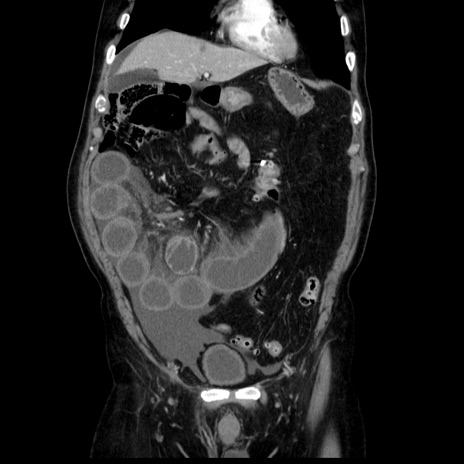

症例30(冠状断像)

【症例】80歳代男性

【主訴】臍周囲痛

【現病歴】約6時間前から臍下部痛が出現。次第に腹部膨隆・背部痛も生じてきたため来院。背部痛の場所は変化しない。

【既往歴】腎盂腎炎

【身体所見】意識清明、BT 36.3℃、BP  131/87mmHg、P 87bpm、SpO2 100%(RA)、臍周囲自発痛・圧痛あり、反跳痛なし、自発痛部位に一致して板状硬あり、腹部膨隆、腸雑音減弱、CVA tenderness両側陰性。

【データ】WBC 19600、CRP 0.33